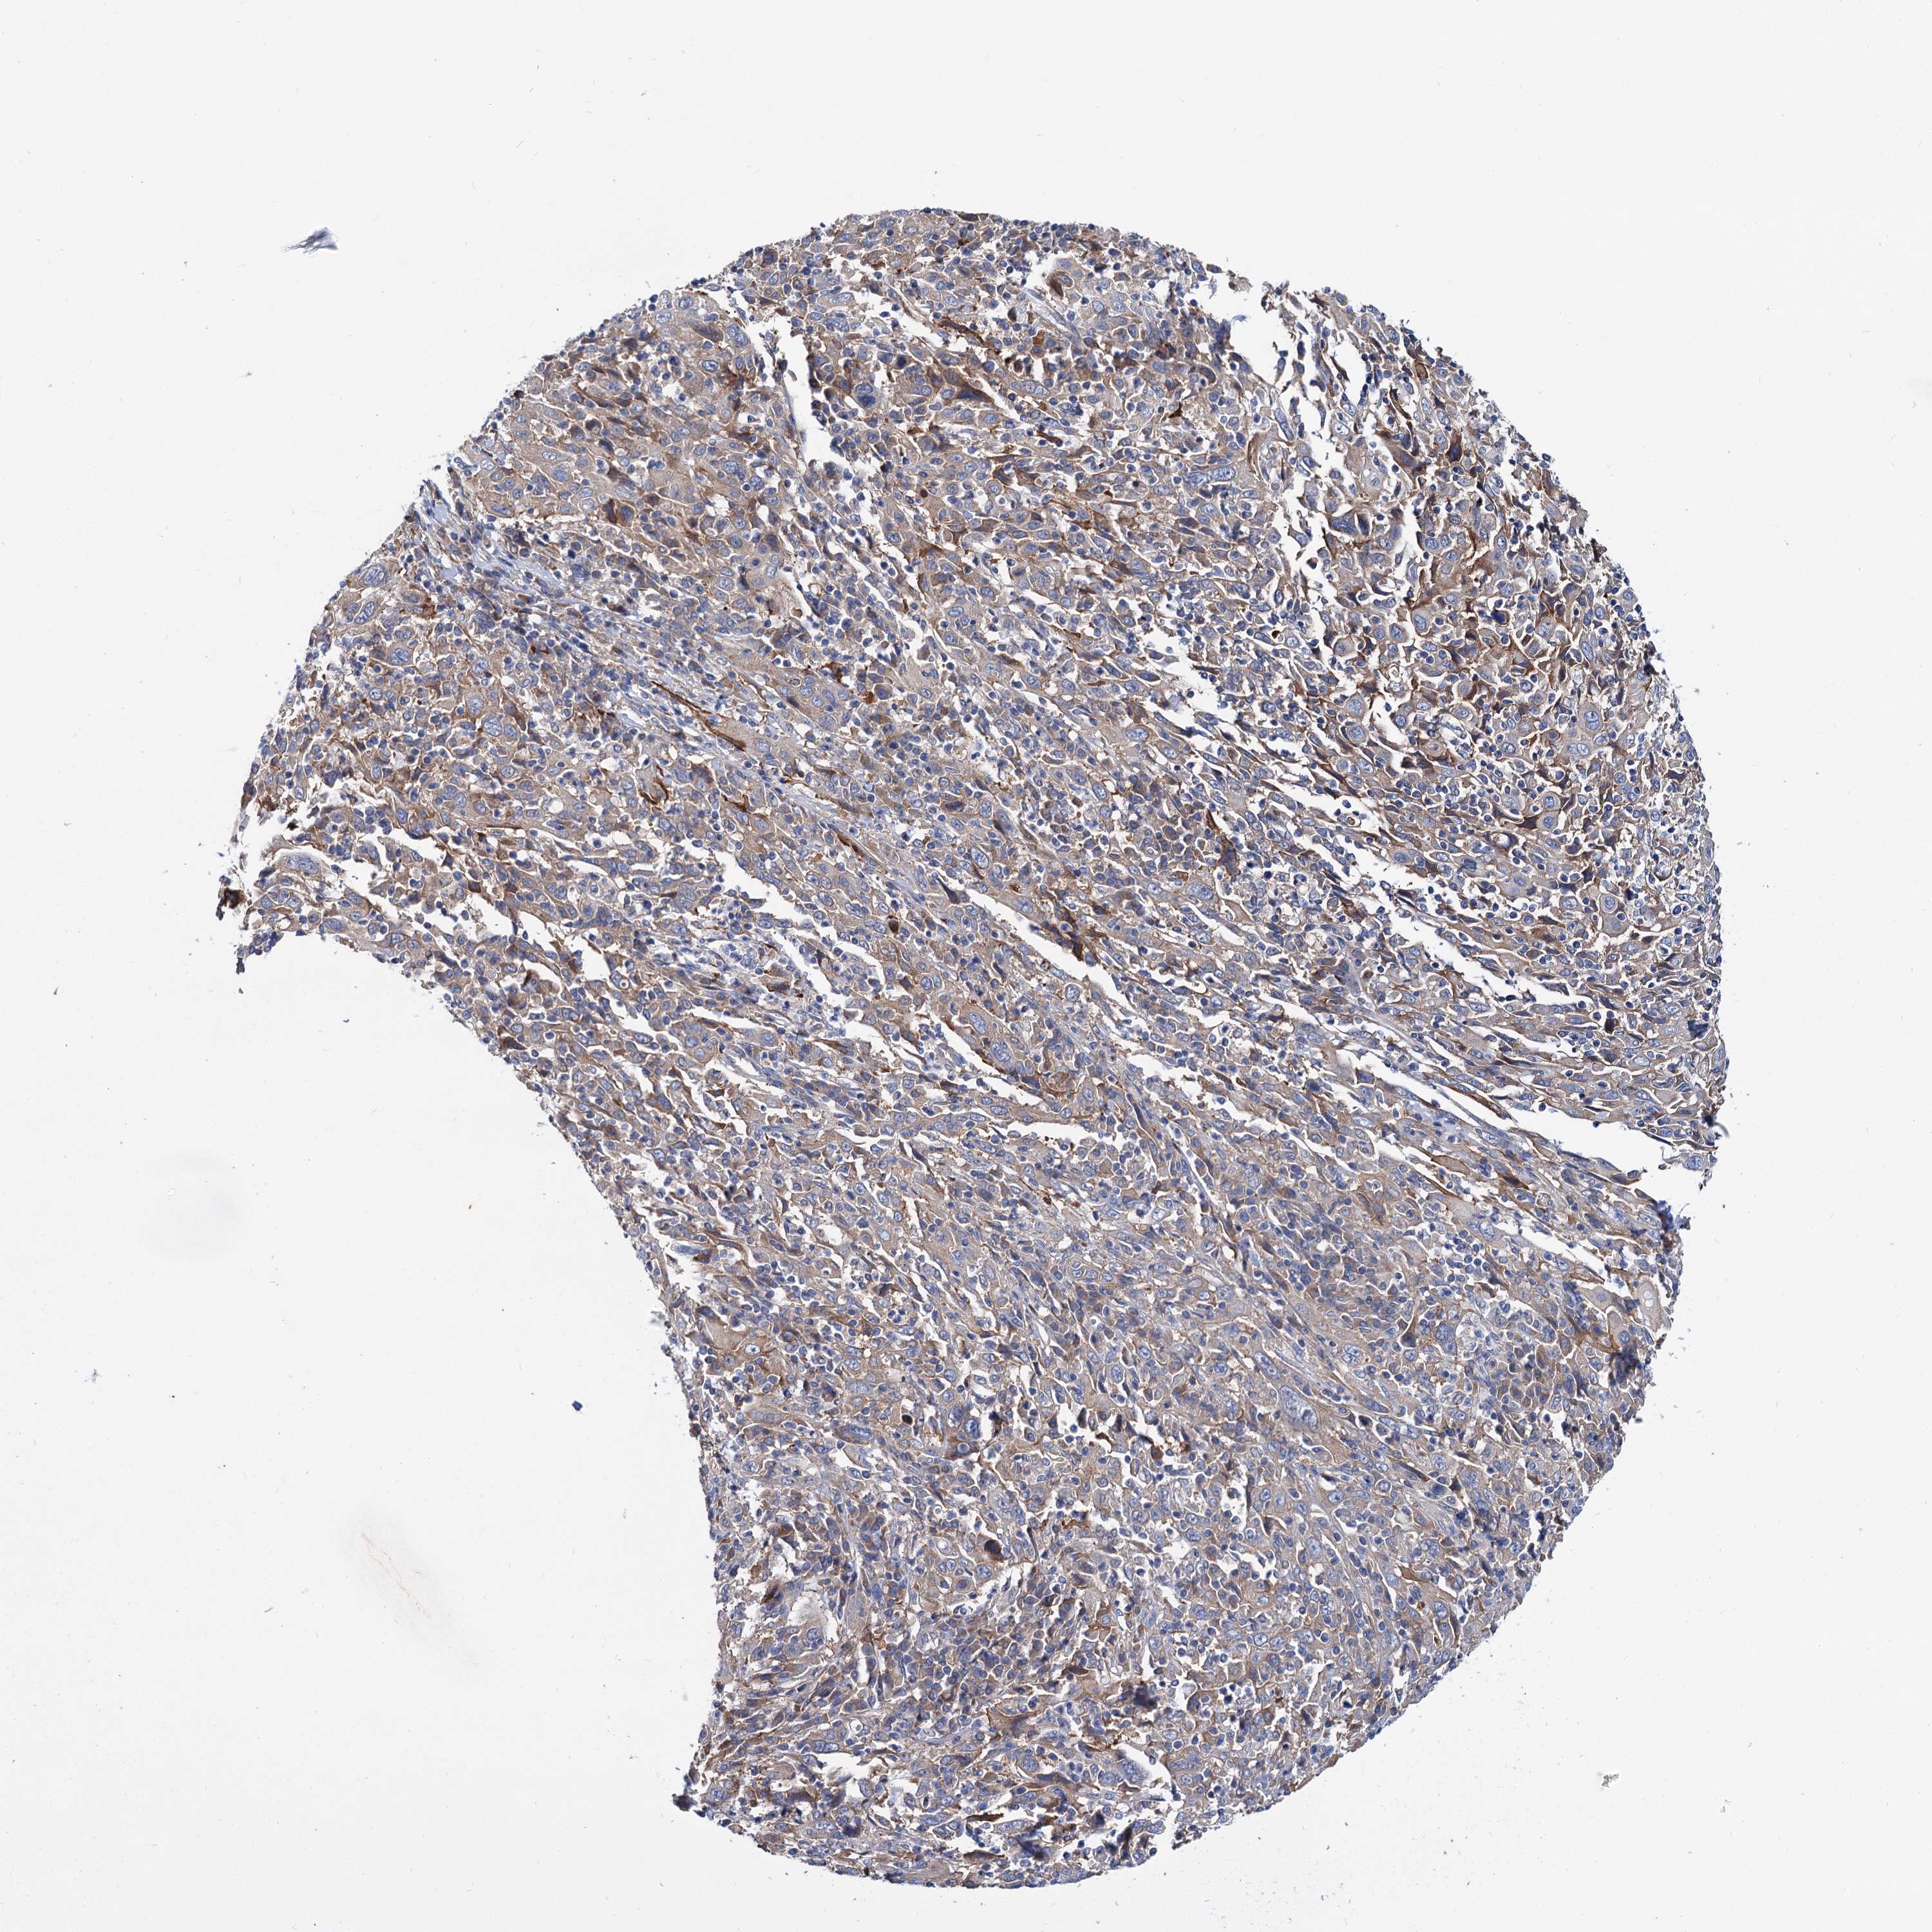

CERVICAL CANCER - Protein expressioni

A mouse-over function shows sample information and annotation data. Click on an image to view it in a full screen mode. Samples can be filtered based on level of antibody staining by selecting one or several of the following categories: high, medium, low and not detected. The assay and annotation is described here.

Note that samples used for immunohistochemistry by the Human Protein Atlas do not correspond to samples in the TCGA dataset.

Antibody stainingi

Antibody staining in the annotated cell types in the current human tissue is reported as not detected, low, medium, or high, based on conventional immunohistochemistry profiling in selected tissues. This score is based on the combination of the staining intensity and fraction of stained cells.

Each image is clickable and will lead to virtual microscopy that enables deeper exploration of all samples and also displays staining intensity scores, fraction scores and subcellular localization as well as patient and tissue information for each sample.

Antibody HPA038793

Antibody HPA053691

Staining

High

Medium

Low

Not detected

Intensity

Strong

Moderate

Weak

Negative

Quantity

>75%

75%-25%

<25%

None

Location

Nuclear

Cytoplasmic/membranous

Cytoplasmic/membranous,nuclear

Squamous cell carcinoma, NOS

Adenocarcinoma, NOS